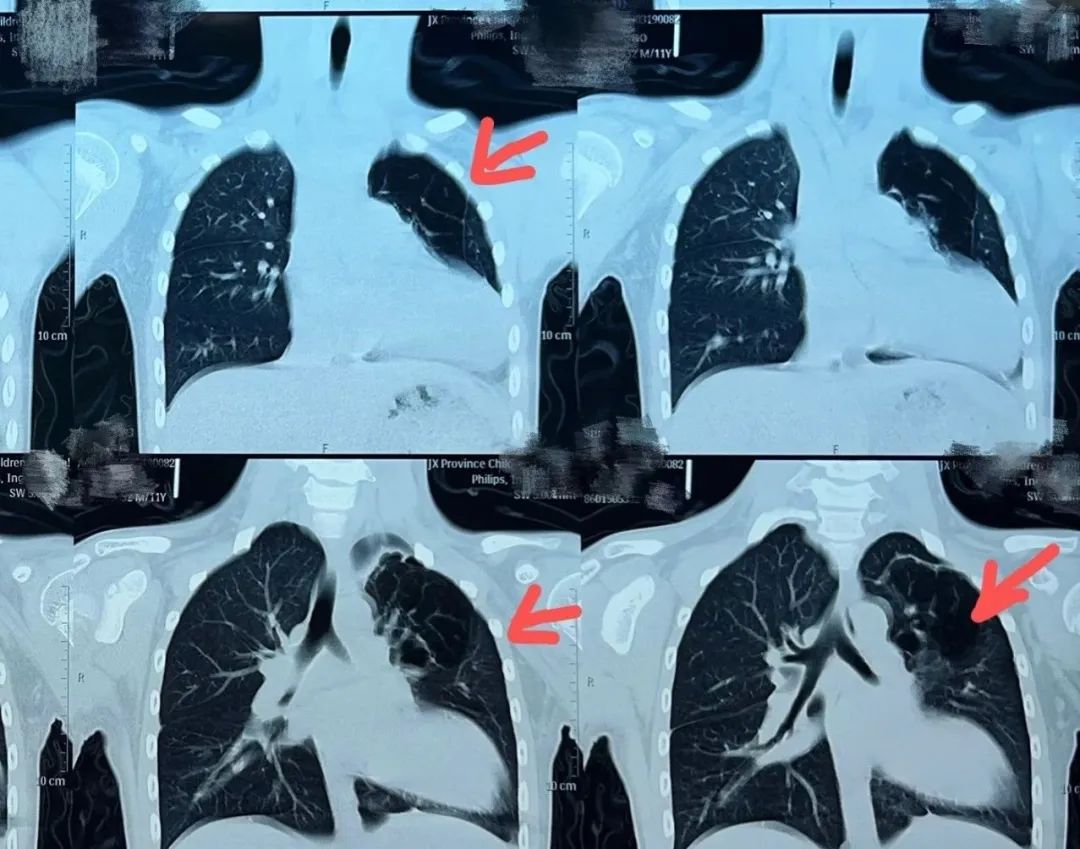

江西鹰潭11岁男童小东(化名)因为咳嗽咳痰、痰中带血、高热在当地多家医院就诊,效果不佳仍反复发作,于是来到江西省儿童医院心胸外科门诊,经过详细的检查发现罪魁祸首是左上肺的多个肺囊泡,肺囊泡导致小东反复的肺炎。

“小东反复咳嗽咳痰,痰中带血,感染重,已经出现胸痛症状,而且检查评估发现胸腔内组织粘连、心脏心包及纵隔胸膜缺失,心脏完全裸露在胸腔内,病变组织与心脏相邻,在狭小的空间内,手术操作难度较大,但是这个手术必须做,否则囊泡会导致肺部反复炎症使肺功能进一步受损。” 心胸外科主任医师涂洪强在病情分析时说道。